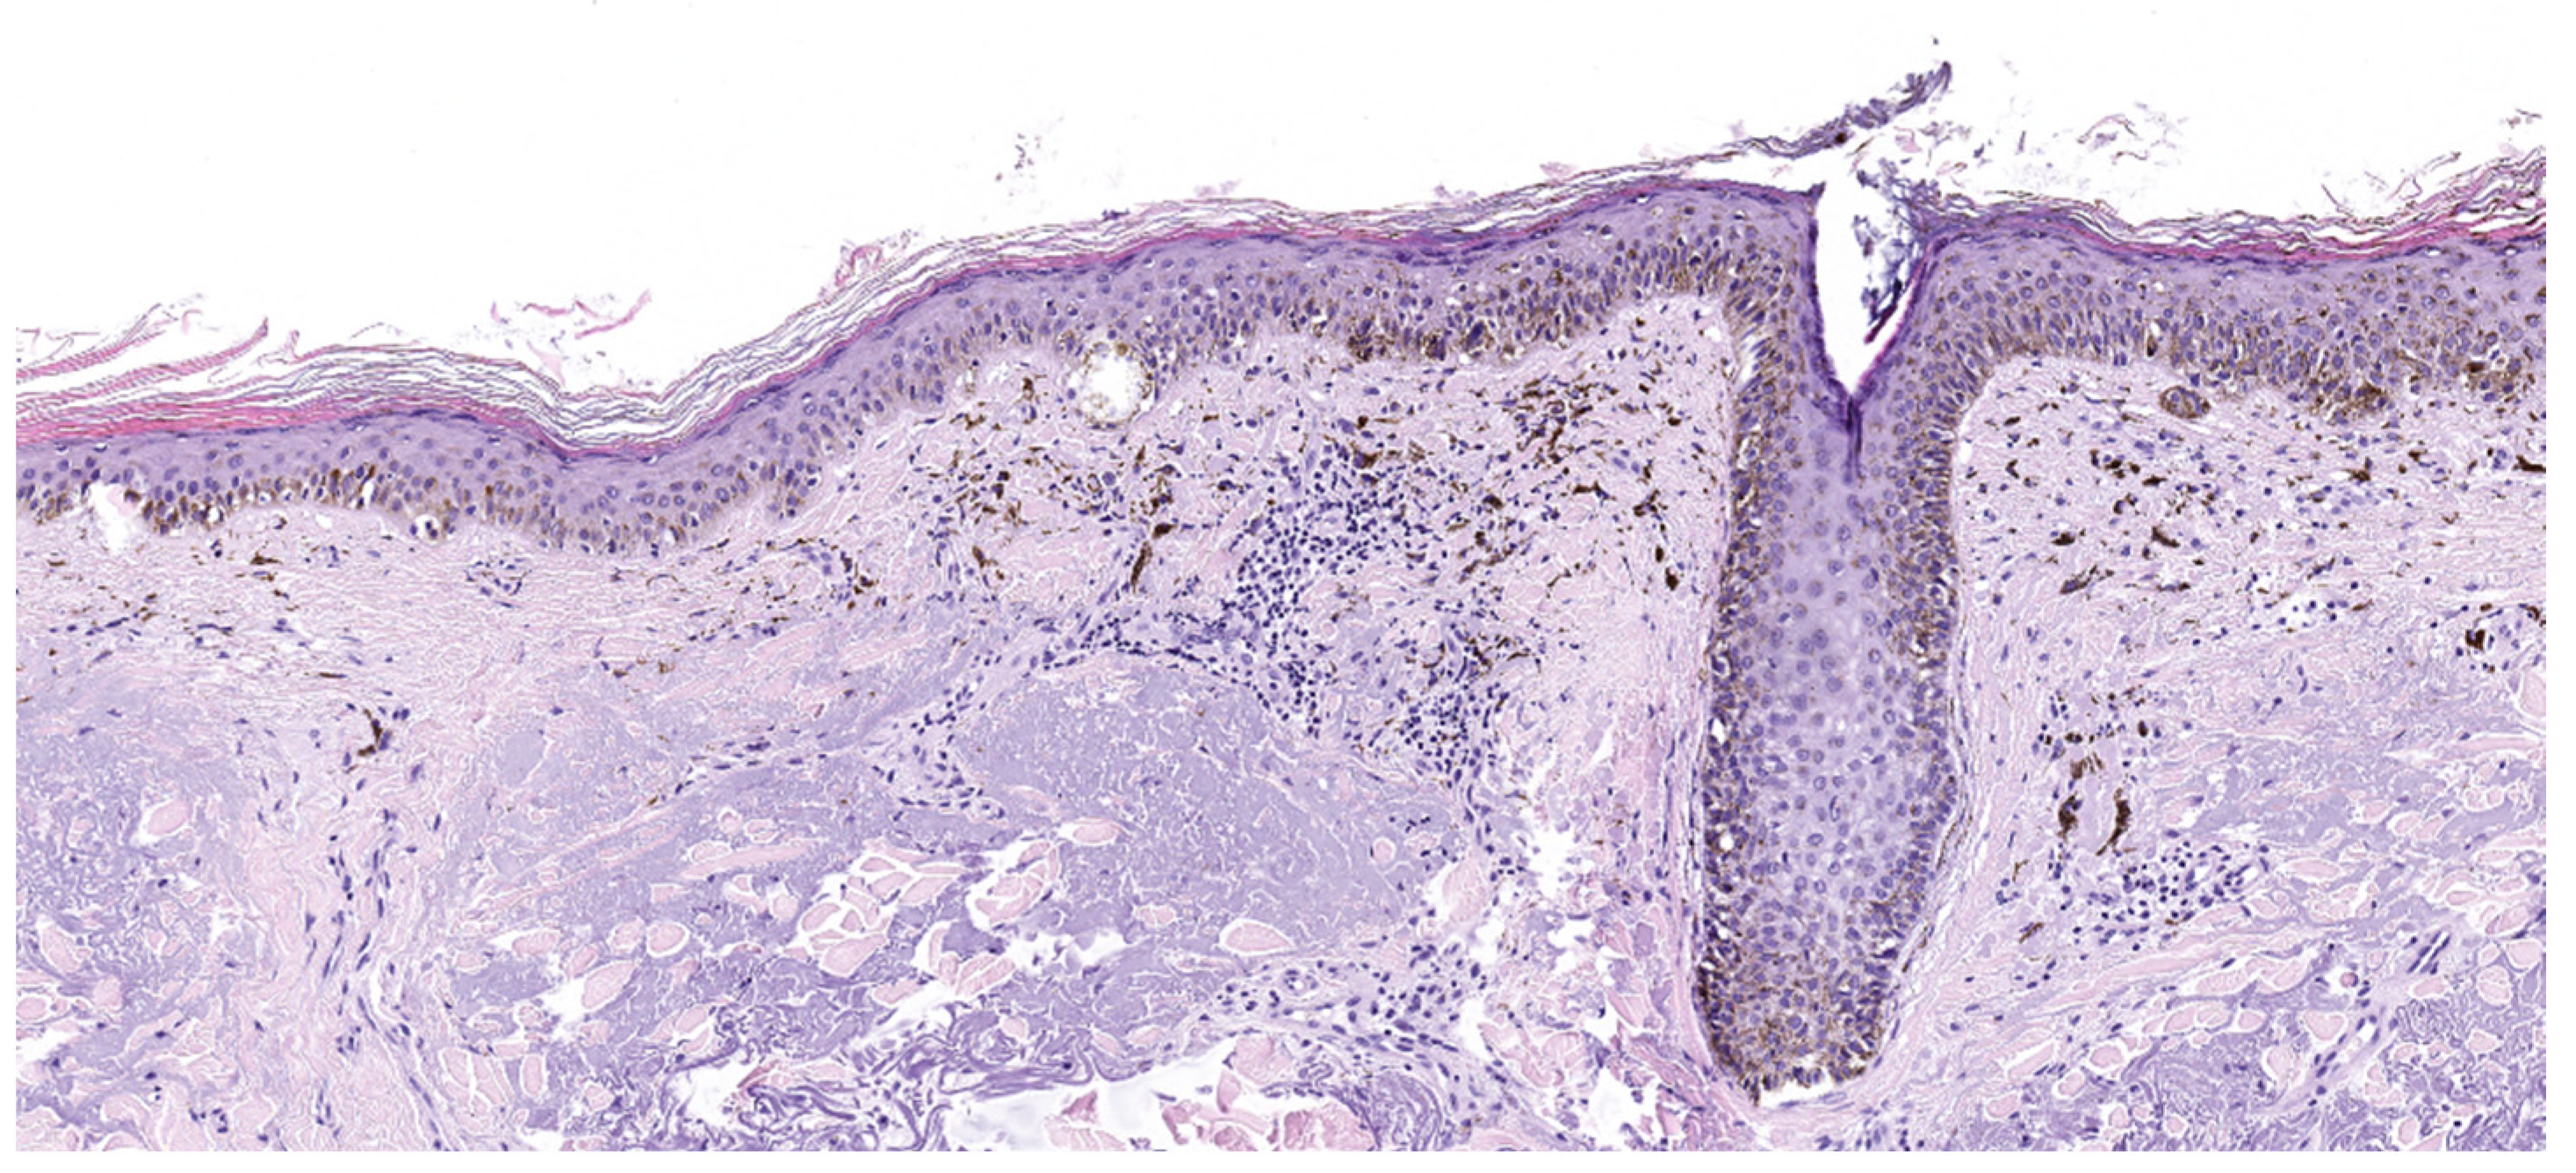

4.1. Superficial Spreading Melanoma